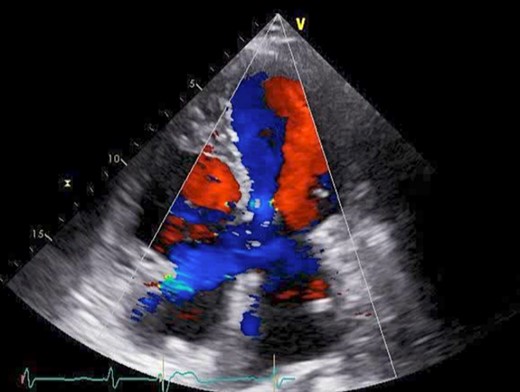

The patient was followed up as an outpatient since 2010 for incomplete AVSD and congestive heart failure by the Cardiovascular Surgery Department at our hospital. She did not wish to undergo surgery; therefore, we continued to follow her as an outpatient. Mitral regurgitation (MR) III-IV and mitral valve deviation was detected by echocardiography at approximately 2022, with worsening heart failure symptoms (New York Heart Association (NYHA) class III status). Echocardiography revealed an ejection fraction (EF) of 65%; severe MR; mean pulmonary artery pressure (PAP) of 32 mmHg; left-to-right shunt flow; left ventricular dysfunction (LVDd) of 48 mm; LVDs, 32 mm; and cleft mitral valve (Fig. 1). Chest radiography revealed a cardiothoracic ratio (CTR) of 58% and a costophrenic angle (CPA) sharp (Fig. 2). Cardiac catheterization revealed a Qp/Qs ratio of 2.6. Therefore, we performed a mitral valve repair and patch closure of the primum ostium defect.

Preoperative cardio echography showing fraction EF 65%, MR severe, mean PAP 32 mmHg, left-to-right shunt flow, LVDd 48 mm, LVDs 32 mm, and a cleft mitral valve.